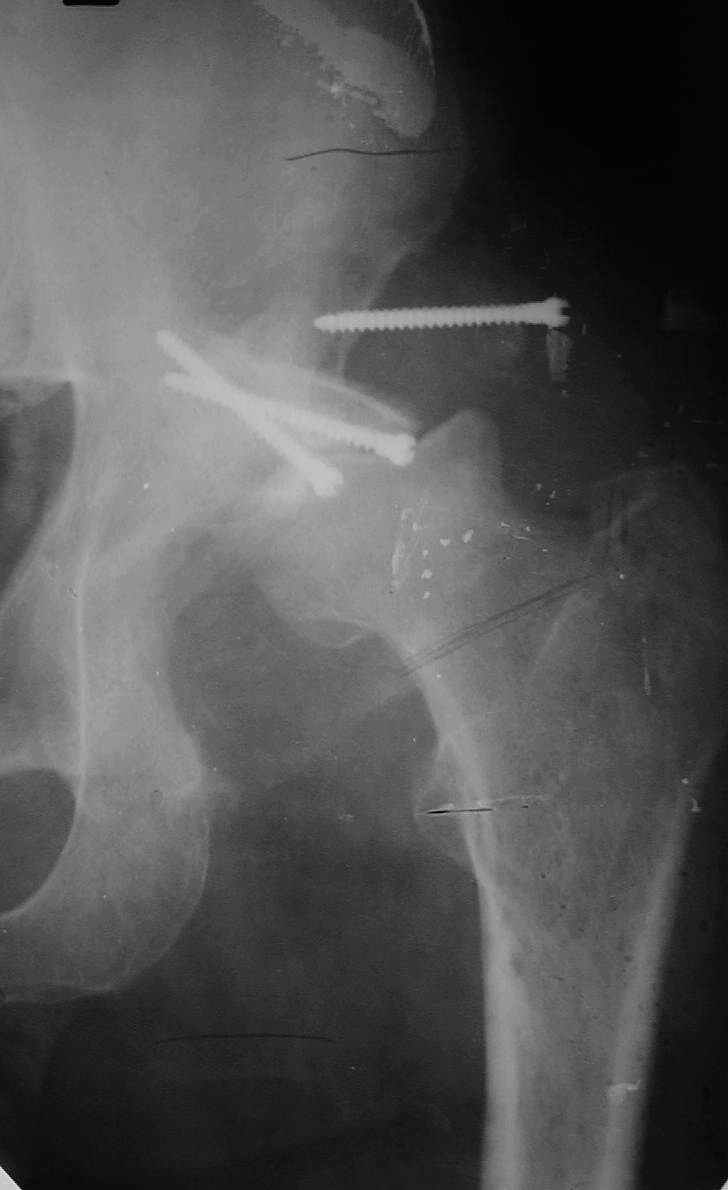

РАВ> Есть ли у Вас примеры установки протеза при обширных дефектах впадины?

РАВ> Какой был самый большой дефицит задней колонны, какой срок наблюдения,

РАВ> довольны ли Вы результатом?

Максимальные сроки наблюдения 5-6 лет. С появлением современных эндопротезов результаты сравнимы с первичным протезированием при обычном КА. Но, каждая операция нестандартная и требуется

тщательнейшее планирование каждого шага и необходимо иметь несколько запасных вариантов.

Схематично можно сказать так - если есть контакт с 60% и более ВВ, то этого достаточно для последующей биологической фиксации чашки. Опять же НО, мы стараемся "подрыться" фрезами так, что бы был приемлимый упор чашки, а фиксация аутотрансплантата головки была прочной без каких либо дефектов и зазоров.

РАВ> В предлагаемой ситуации имеется последствия перелома задней колонны,

РАВ> что значительно больше усугубляет ситуацию, чем банальный дефект

РАВ> заднего края, и костного материала из головки может просто не хватить,

РАВ> тем более что в таком случае как раз вся нагрузка должна лечь на эту

РАВ> несчастную костную пластику.

Если у Вас есть дефект крыши, то никакая пластика не выдержит, лучше сразу ставить опорные кольца, все зависит от локализации костного дефекта.

1 год